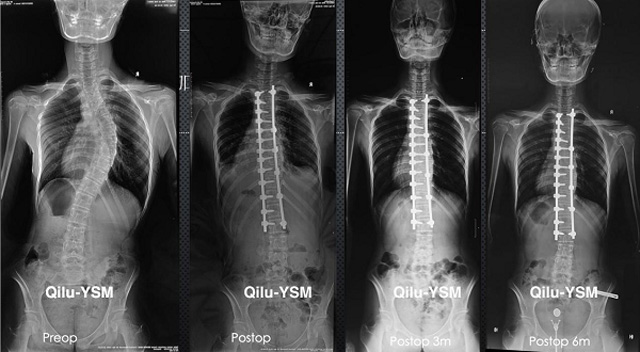

悬吊DR-全电动型机架DR检查主要用于胸部、四肢、关节、脊柱等,主要检查肺部炎症、肿瘤、结核病、四肢骨关节的骨折、四肢关节、脊柱外伤等。DR就是X光,是一种数码影像,曝光时间很短,摄像量很小,影像质量也很好,可以说是一种替代CR的方法。DR检查有其局限性,需要做CT平扫等检查,周围淋巴结的转移以确定病变的良恶性、范围、大小、与邻近组织的关系。